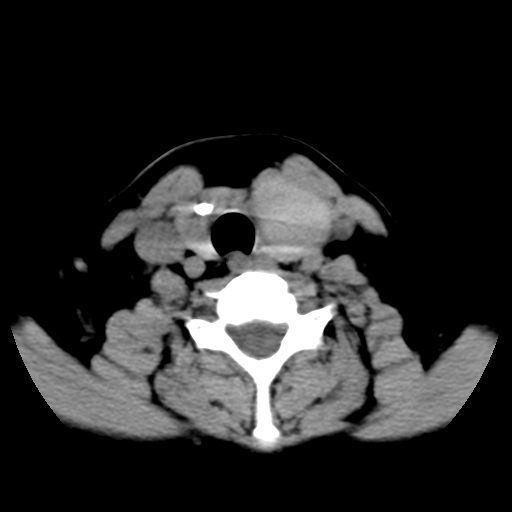

标题: CT25491:女,55岁,发现左侧甲状腺肿块一个月。 [打印本页]

女,55岁,发现左侧甲状腺肿块一个月,彩超示:甲状腺多发结节伴左叶结节液化。

左右叶都有,峡部也受累,有钙化,考虑结甲可能性大。

甲状腺东西特异性不强,结节很小有很多是恶性,有的很怕人却是良性。